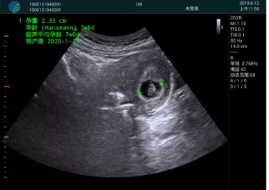

病例一:

清晰顯示孕囊,通過軟件包計(jì)算孕齡7w+6d

M20實(shí)時(shí)引導(dǎo),術(shù)中清晰顯示孕囊被破壞和抽吸針的過程,清晰顯示吸引針

抽吸結(jié)束后縱切子宮,孕囊已被完全抽吸,未見明顯殘留

橫切子宮,發(fā)現(xiàn)右側(cè)宮腔靠近宮角處有少許脫模樣殘留

M20引導(dǎo)下,抽吸針找到右側(cè)宮角處再次清掃

二次抽吸后再次進(jìn)行超聲檢查,宮腔未見殘留,宮腔線清晰顯示

超聲引導(dǎo)下可視化人流是技術(shù)安全性的保障,一般對人流術(shù)設(shè)備預(yù)算不高,M20具備婦產(chǎn)科軟件包,且穿透力圖像質(zhì)量好,既滿足人流引導(dǎo)需要,也可用于床旁超聲的需求。